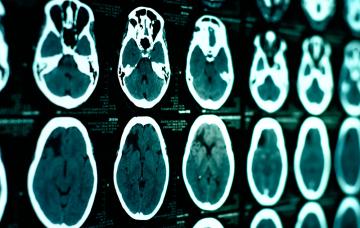

Diagnóstico de parálisis cerebral

El diagnóstico de parálisis cerebral se basa en observar al niño, y en pruebas que determinan los trastornos asociados o la diferencian de otras patologías.